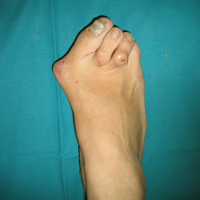

• Κότσια - Εξαρθρήματα μεταταρσίων